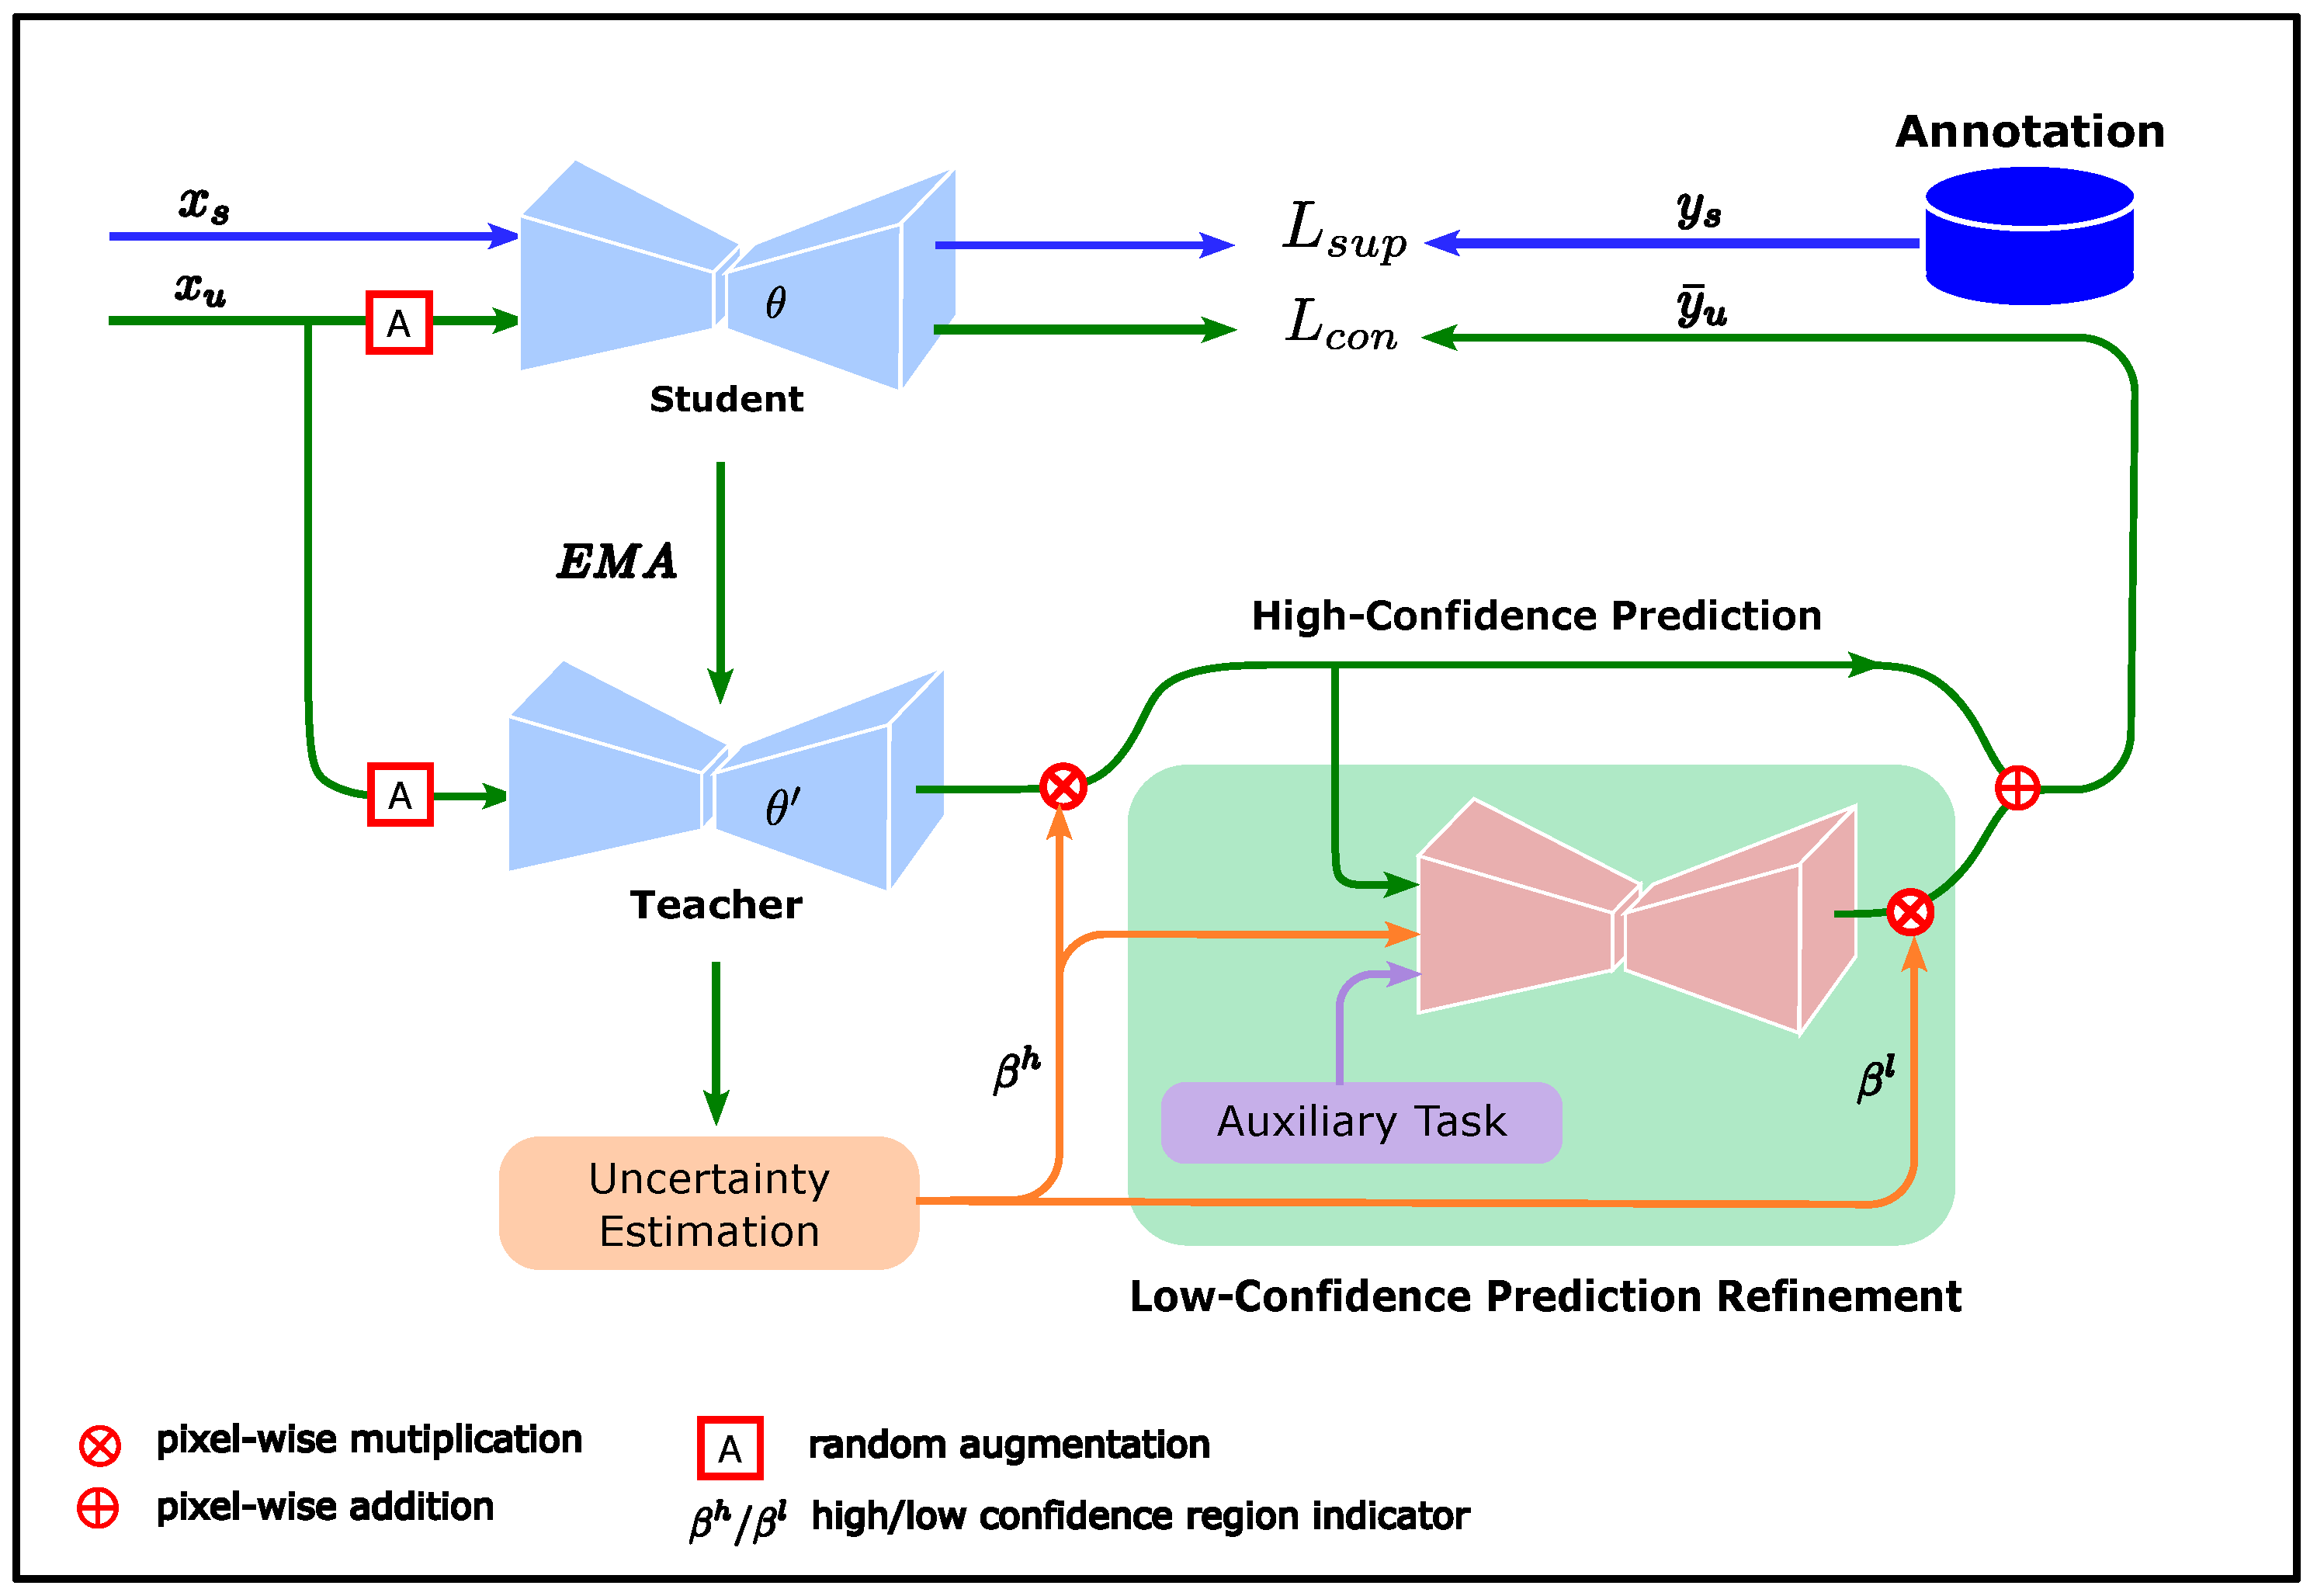

2.2. Overview of Methods

2.3. Uncertainty Estimation

2.4. Low-Confidence Prediction Refinement

- Consistency regularization constraints are constructed using unlabeled data from the validation set to participate in model training. In deep learning models, it is often assumed that the training set and the dataset have the same data distribution, an assumption that is often difficult to satisfy in practice, especially because medical imaging data often contain information related to the data domain introduced by specific device parameters. If the loss function contains only information relevant to the training set, the performance of the model on the test set largely depends on its similarity to the training set data. By adding a consistency regularization term constructed from the validation set data to the loss function, the output of the model on different datasets is constrained by the consistency regularization. The results in Table 3 show that both the MT method and our proposed method reduce the OUSR in the test set in this way.

- Leveraging domain-related information contained in the low-confidence prediction region. Recent studies on domain adaptation [42,43] show that models tend to produce low-confidence predictions when the target and source data domains differ. This suggests that low-confidence predictions may be caused by the presence of domain-related information in the target data domain that has not been learned by the model. Directly constructing consistency regularization terms using these low-confidence predictions can cause the model to suffer from confirmation bias. Meanwhile, using the strategy of discarding low-confidence predictions, as in recent studies, loses the opportunity to fully learn the domain-relevant information from the dataset. We draw on the experience of doctors when performing delineation and refine the low-confidence predictions using high-confidence predictions as well as the learned prior to enable the model to fully learn the domain-relevant information from the dataset. In the experiments, our method outperformed the other two methods in all evaluation metrics.

- The utilization of prior knowledge reduces the dependence of target predictions on the teacher predictions and improves the accuracy and stability of model training. The GAN used in the low-confidence predictions refinement module learns the anatomical prior of the breast and pectoral muscle in mammograms, which provides regularization constraints for the target predictions used in the student model training. Therefore, fluctuations in the performance of the teacher model will not have a large impact on the target predictions. Moreover, GAN uses domain-independent semantic features as input, and its main reliance on the teacher model is the high-confidence predictions, which are usually easy to learn. Thus, the low-confidence prediction refinement module can provide regularization constraints for target predictions that do not vary by the data center.